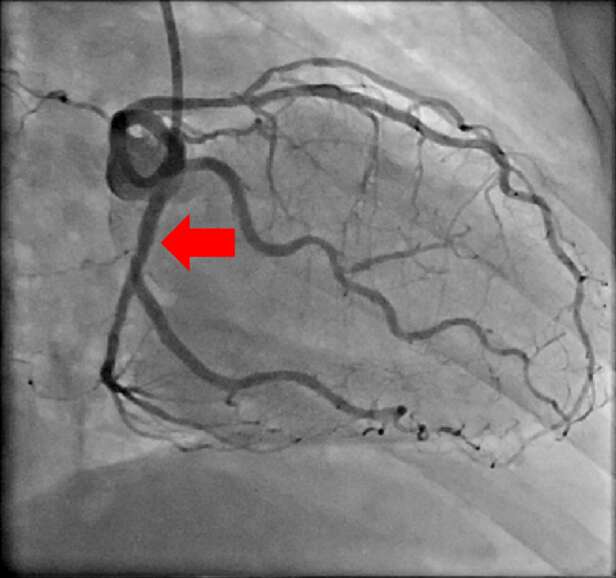

【治療例3:狭心症ステント拡張術】

心臓に栄養を送る血管を冠動脈と呼びますが、冠動脈が狭窄すると心筋梗塞や狭心症を発症します。

冠動脈の狭窄又は閉塞を専用の治療器具を用いて治療していきます。

治療前

赤矢印の冠動脈が狭窄している

治療後

狭窄していた冠動脈にステントを留置し、血流が元に戻っている